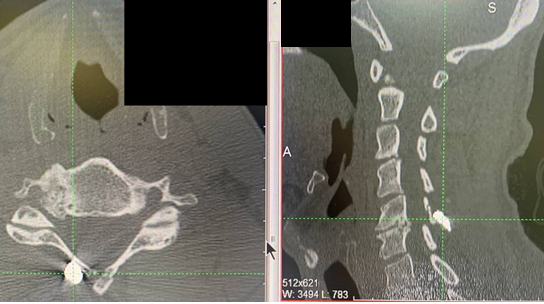

КТ-исследование шейного отдела позвоночника: инородное тело в мягких тканях шеи. Перелом задней дужки справа и остистого отростка СV

Эндоскопическое удаление инородного тела (осколка) из межпозвонкового отверстия на уровне CV справа.